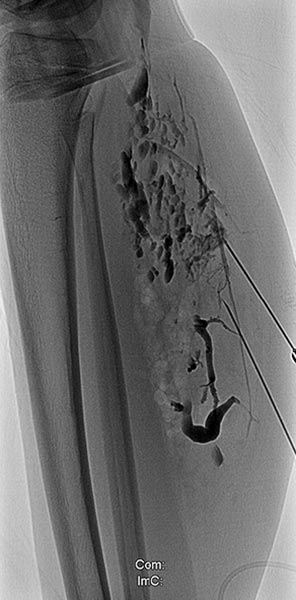

Erneute Sklerosierungsbehandlung 3 Monate nach der ersten Behandlung mit Aethoxysklerolschaum 3 % nach Direktpunktion mit einer Nadel unter sonographischer Steuerung. Die weiter proximal gelegenen Anteile der venösen Malformation sind zum Teil verschlossen, die noch offenen Kanäle deutlich verkleinert. Keine Kommunikation mehr mit dem tiefen Leitvenensystem. Inzwischen war zum Beinlängenangleich rechts eine temporäre Epiphyseodese mit vorübergehender Klammerung der Wachstumsfugen durchgeführt worden.

Es erfolgte eine erneute Punktion weiter proximal am Unterschenkel, da hier sonographisch noch offene Anteile der venösen Malformation nachweisbar waren. Nach Anspritzen kontrastieren sich nur noch wenige, kleinlumige Abschnitte der Malformation. Sklerosierungsschaum in den Hohlräumen des distalen Anteils der Malformation (als Aufhellung sichtbar).